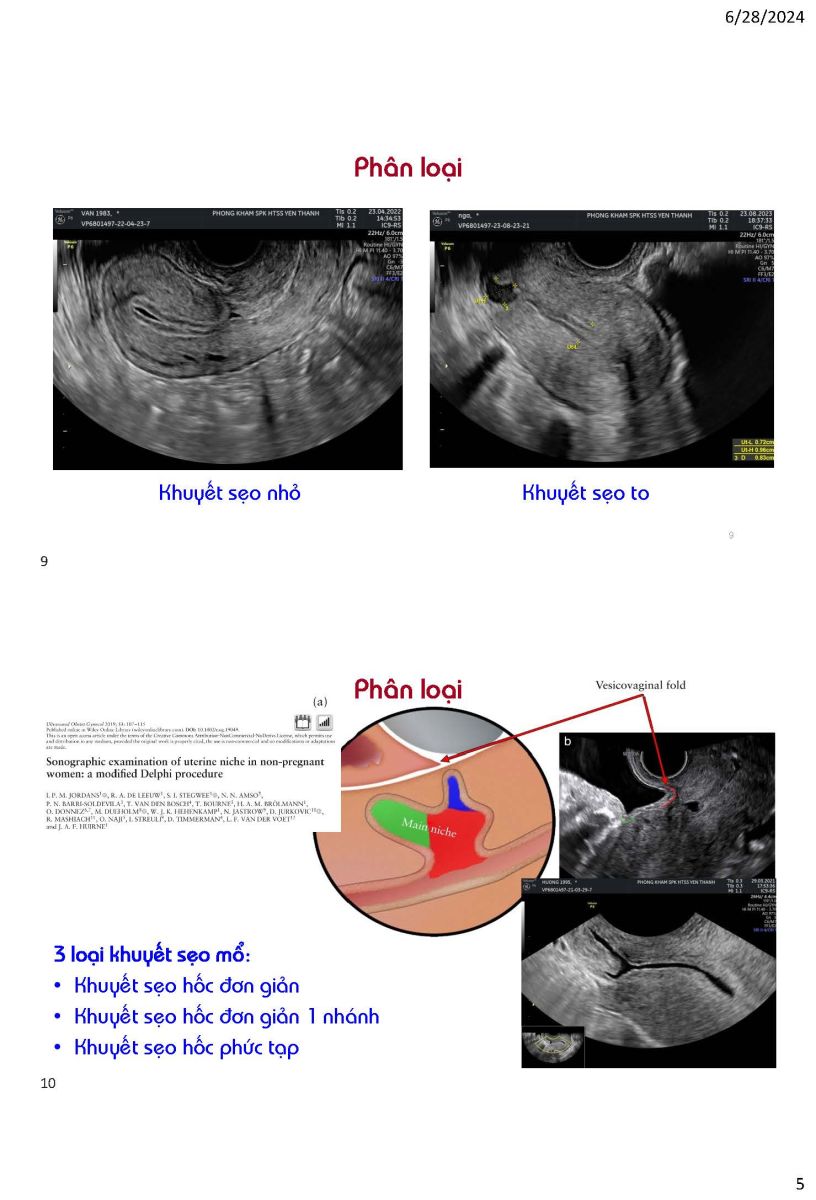

Ứng dụng siêu âm trong quyết định phương pháp can thiệp khuyết sẹo mổ lấy thai